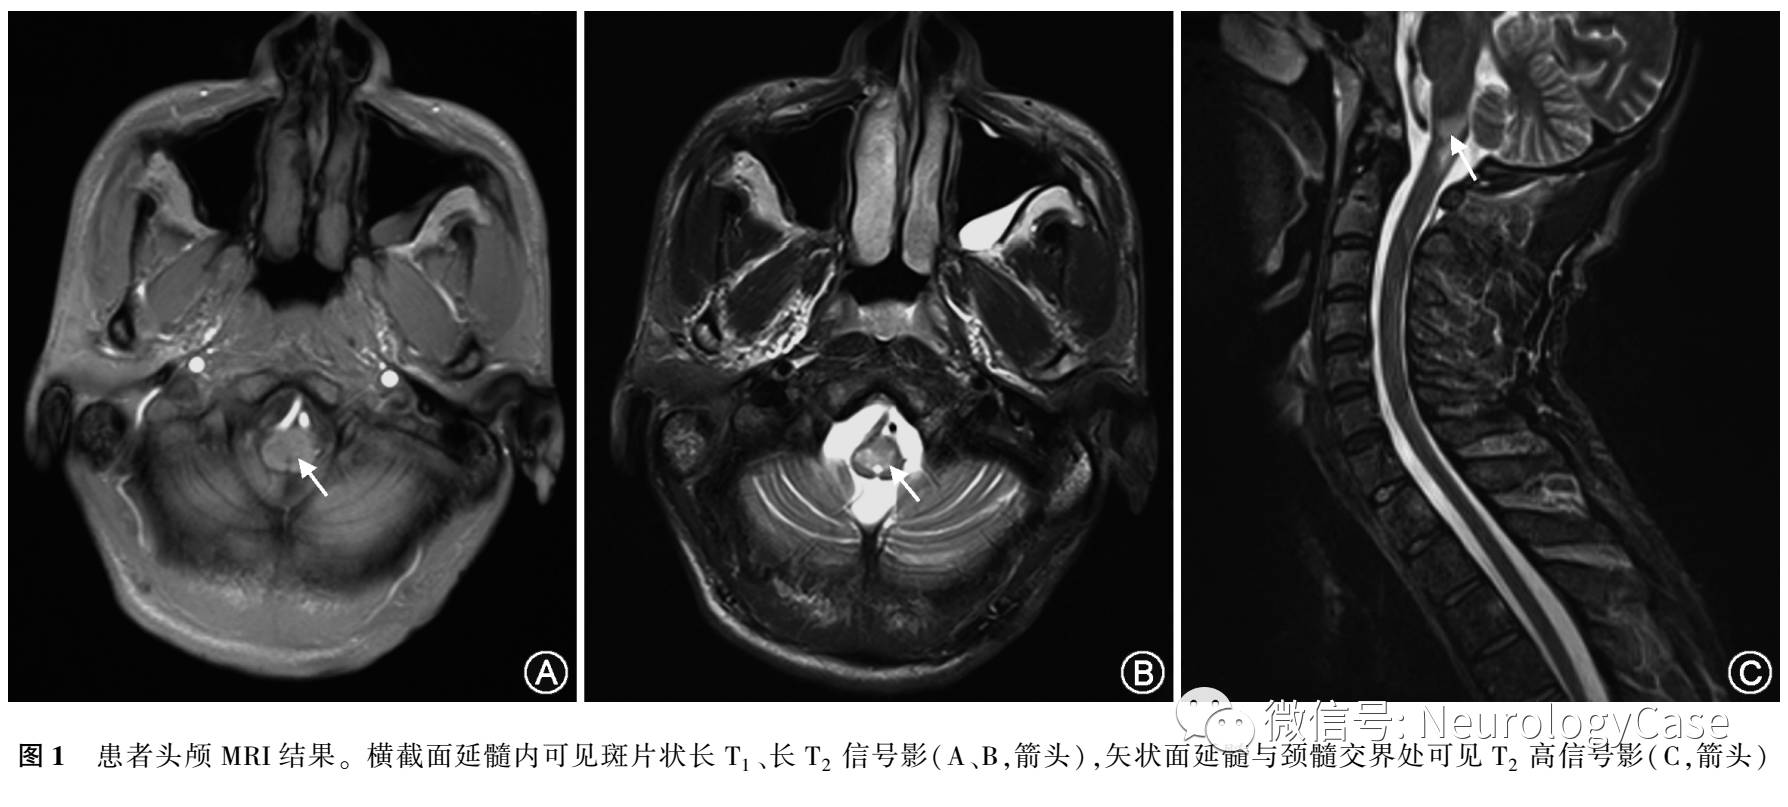

患者男性,43岁,以“右面部发麻伴头晕20余天,头痛2d”为主诉入院。20余天前患者被电焊光闪眼后出现右侧面部发麻,至当地诊所按“感冒”处理,2d后出 现头晕,表现为视物旋转、不敢睁眼,伴呃逆、恶心、非喷射性呕吐,呕吐物为胃内容物,无发热、视物重影、肢体麻木无力,就诊于驻马店市人民医院,予以口服药物(具体不详)治疗后无好转,遂至郑州颐和医院行腰椎穿刺脑脊液检查未见明显异常,头颅MRI示:脑干病变。按“脑炎”予以激素、抗病毒、改善循环、止晕、护胃等治疗半个月后复查头MRI病灶较入院时病变范围减小,症状减轻后出院。患者本次入院2d前开始出现右侧头痛,呈阵发性针刺样疼痛,伴双下肢麻木、发凉、无力,自觉头晕、恶心加重,为求进一步诊治来我 院。神经科体检:意识清楚,言语流利,高级智能活动正常,双侧瞳孔等大等圆直径3mm,对光反射灵敏,眼球运动充分,双眼可见水平及垂直眼震,余脑神经体检未见明显异常,四肢肌张力正常,双上肢肌力Ⅴ级,双下肢肌力Ⅳ级,双上肢腱反射(++),双下肢腱反射(+),双手快速轮替试验正常,双手指鼻快准,双下肢膝上10cm以下感觉倒错,深感觉正常,双侧霍夫曼征(-),巴宾斯基征(-),余体检欠配合。辅助检查:血尿便三大常规、红细胞沉降率、C反应蛋白、凝血功能、肝肾功能、电解质、血脂、甲状腺功能及甲状腺抗体、风湿免疫全套无明显异常;脑脊液常规、生化、细胞未见异常,IgG指数0.82(正常值0.3-0.7),寡克隆区带(-),脑脊液AQP4抗体阳性(细胞免疫荧光法)。头颅MRI平扫+增强示:延髓异常信号,炎性或脱髓鞘病变可能大。颈胸腰椎MRI示:延髓与颈髓交界处异常信号,炎症或脱髓鞘可疑 待查(图1)。肌电图示左腓肠肌神经源性改变,左腓肠神经末梢感觉传导速度减慢,左正中神经F波出现率异常,潜伏时未见异常;运动诱发电位示左下肢锥体束传导未见异常,脊髓刺激周围段传导延迟;体感诱发电位示左下肢深感觉传导路P40未引出;视觉诱发电位示双眼P100未引出。